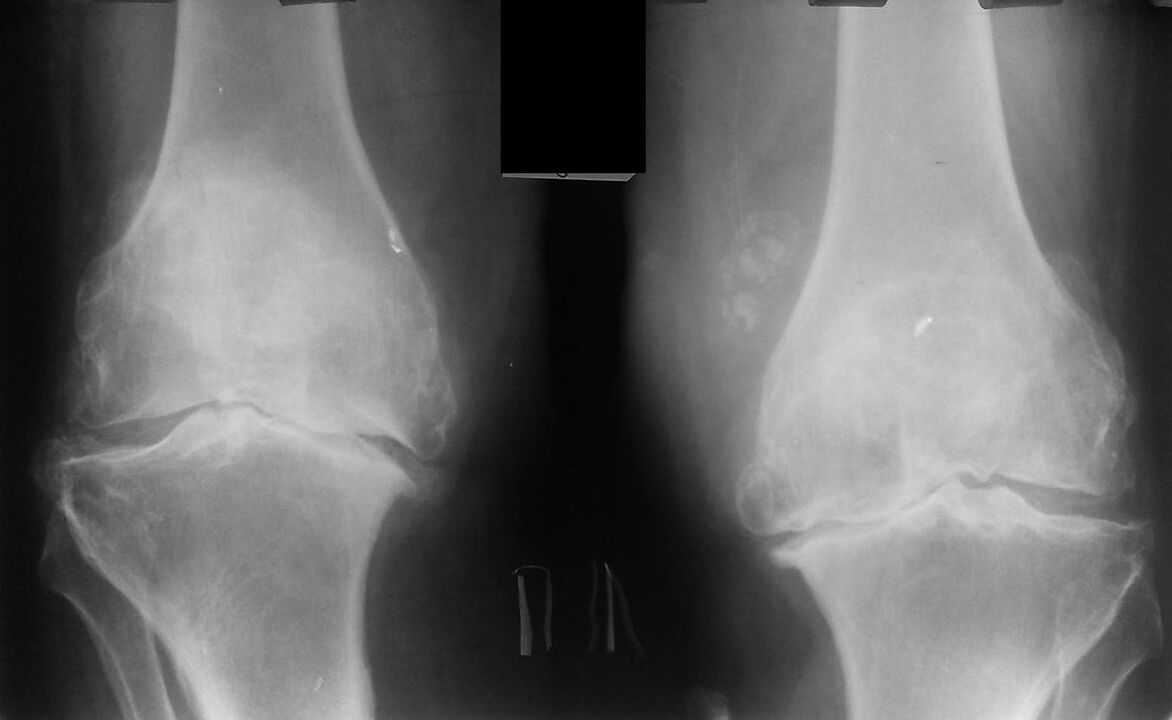

ceļa locītavas rentgens ar artrozi

Šī diagnoze tiek noteikta, pamatojoties uz pacienta sūdzībām, izmeklēšanas datiem, slimās locītavas palpāciju un rentgena izmeklēšanu.

Rentgens ir standarta izpētes metode, kas ļauj apstiprināt diagnozi, noteikt patoloģisko izmaiņu pakāpi, uzraudzīt procesa dinamiku, kā arī ļauj izslēgt citus patoloģiskus procesus (piemēram, audzējus) stilba kaulā un augšstilbā. .

Jāņem vērā, ka primārās izmaiņas ceļa locītavas struktūrās rentgenogrāfijās var nebūt. Pēc tam tiek noteikta locītavas spraugas sašaurināšanās un subhondrālās zonas sablīvēšanās. Ciskas kaula un īpaši stilba kaula locītavu gali paplašinās, kondilu malas kļūst smailas.

Diagnostikas palīgmetodes ir CT (datortomogrāfija) un MRI (magnētiskās rezonanses attēlveidošana), kas ļauj detalizētāk izpētīt patoloģiskās izmaiņas kaulu struktūrās un identificēt izmaiņas mīkstajos audos.